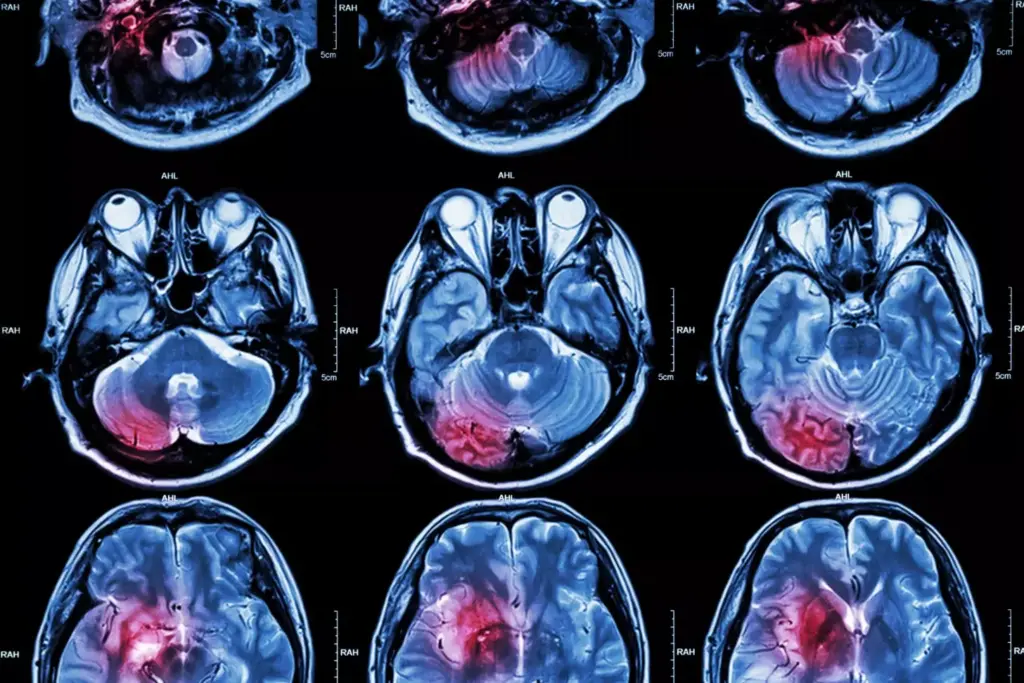

How are brain tumors diagnosed?

Doctors use MRI or CT scans to find brain tumors. They might also take a biopsy to confirm the type of tumor.